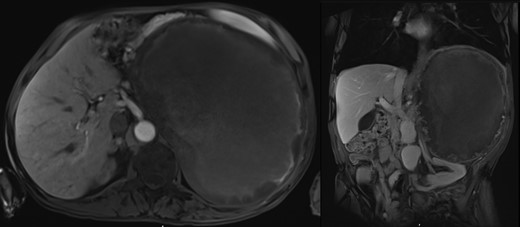

A seventy-four-year-old gentleman was referred with a left loin pain and a large abdominal mass. His symptoms included headaches, loss of appetite, chronic anemia and weight loss with a documented systolic blood pressure of over 200 mmHg. Abdominal examination showed an obvious large left abdominal mass. MRI scan showed a 25 cm left adrenal tumor (Fig. 1). Endocrinological lab work up was consistent with a PCC.